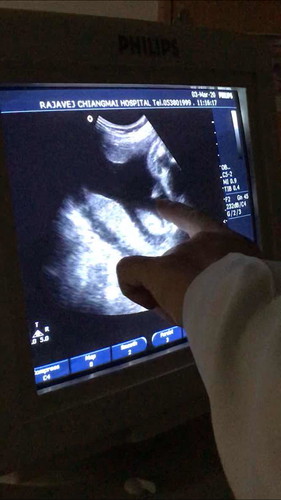

ตอนนี้แม่ท้องได้ 28w5d แล้ว แต่ไม่มีวี่แววของน้ำนมเลย มีแค่คัดตึงเต้าตอนเดือนแรกถึงเกือบๆเดือนสาม กังวลว่าลูกคลอดแล้วจะไม่มีน้ำนมค่ะ แม่ๆบ้านไหนเป็นไหมคะ หรือมีคำแนะนำยังไงบ้างคะ #น้องเป็นเพศชายค่ะ ขอบคุณค่ะ ?